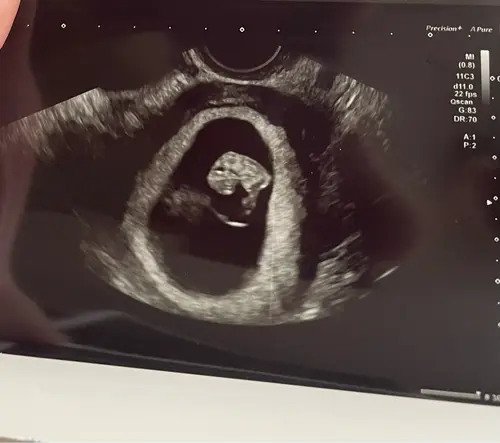

Vandaag, twee weken later, mocht ik weer terugkomen voor een echo, en wat is het al mooi gegroeid! Ik durf voorzichtig blij te zijn en mag vanaf nu ook weer terug naar de verloskundige. 🍀